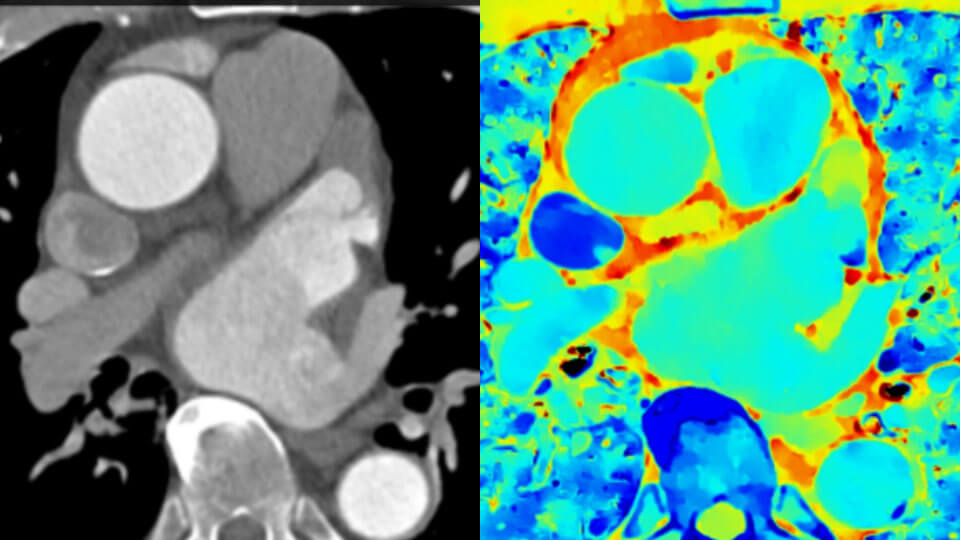

標準のCTの画像(左) スペクトラルディテクタCTの画像(右)

標準のCTでは「対象物がどこにあるか」がわかるのに対し、スペクトラルディテクタデータからは「対象物は何か」が明らかになり、これからは両方の情報を簡単に得られるようになります。情報量の多いスペクトラルデータを重ね合わせることで、組織の特性評価と視覚化が改善され、患者の検査が最適でなかった場合や、偶発病変が見つかった場合に、フォローアップスキャンを行う必要性が低減される可能性があります。

撮像視野の広いスペクトラル心臓イメージングを使用して、お使いの心臓用機能を拡張して向上させることができます。冠動脈のカルシウムブルーミングを低減できます。